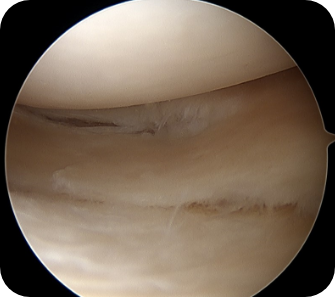

• 2) 관절경하 연골판 봉합술

반월상 연골판 파열 중, 파열된 부분의 혈류공급이 원활하고, 파열면의 상태가 깨끗하여 봉합 시 다시 붙을 가능성이 있는 경우에 찢어진 연골판의 두 부분을 실이나 기구를 이용하여 봉합해 주는 방법입니다.

수술방법

관절내시경을 이용하여 무릎 안을 보면서 여러 기구로 찢어진 부위를 봉합합니다.

• ▲ 무릎 연골판 봉합술 전

• ▲ 무릎 연골판 봉합술 후

수술장점

연골판을 파열전의 모양 및 기능으로 회복시키는 수술입니다. 봉합하여 잘 붙는 경우 파열전의 상태와 똑같은 상태로 돌아갈 수 있습니다. 물론, 봉합된 부위가 붙을 가능성이 떨어지는 경우에는 권하기 힘들며, 부분 절제술, 연골판 이식술 등 다른 수술 방법을 고려해야 합니다.

수술 후 관리법

간단한 내시경 수술이지만 봉합된 부위에 힘이 가지 않도록 안정을 취하여야 합니다. 파열된 위치, 모양, 크기, 봉합방법에 따라 차이가 있지만 일반적으로 1~2 달간의 목발보행 및 2달간의 보조기 착용을 필요로 하게 됩니다. 이후 정상생활로의 복귀는 가능하나 무리한 활동 및 운동은 일반적으로 6~9개월 간에는 제한을 권합니다.